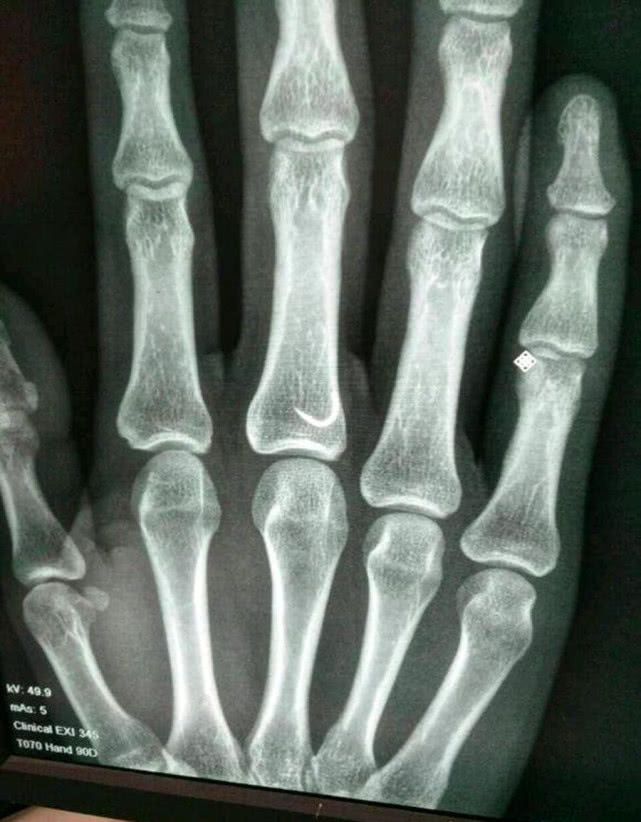

等我把鱼溜翻白了,也顺利的抄鱼上岸了。可就在我放松警惕摘钩时,鱼却突然向外窜,绷紧的鱼线突然弹了回来,一不小心把钩子挂在了自己的手指上。鲜血马上渗出,疼痛难忍,无论如何,却不能取出,因为倒刺已经深入肌肉组织,如果硬拔,要将手指内肌肉组织带出,更是像割肉一样,疼痛啊,眼泪也出来,一时也不能去医院(路远),没有办法。

倒刺鱼钩挂在手上千万别往外拔,人的皮是很厚滴,倒刺挡着根本不可能拔出来,挂上后千万别慌,不要沾到生水,把钩上的线剪断,清除钩把上残留的线头,然后直接捏住钩顺着钩尖的方向穿透皮肤,因为鱼钩是U型的,很容易就穿过来了,鱼钩取出后,用力挤出脏血,直到血液鲜红为止。用干净的棉布或者纸巾包扎,回家后用药物消毒,服用抗生素。虽然创伤小,但也痛,但总比用刀划开强,如果钩把比较大或有圆环等其他大的阻挡的话,用斜口钳剪断钩柄,穿透取出,取出后注意消炎。

之前也有看到钓友被鱼钩刺手,深入到骨头之中了,去医院,医生给划了个2~3公分口子,还缝了3~4针。想想去医院除了手疼还会心疼就自己处理了。如大家有更好的方法请贡献出来,钓鱼人谁没被挂过啊。